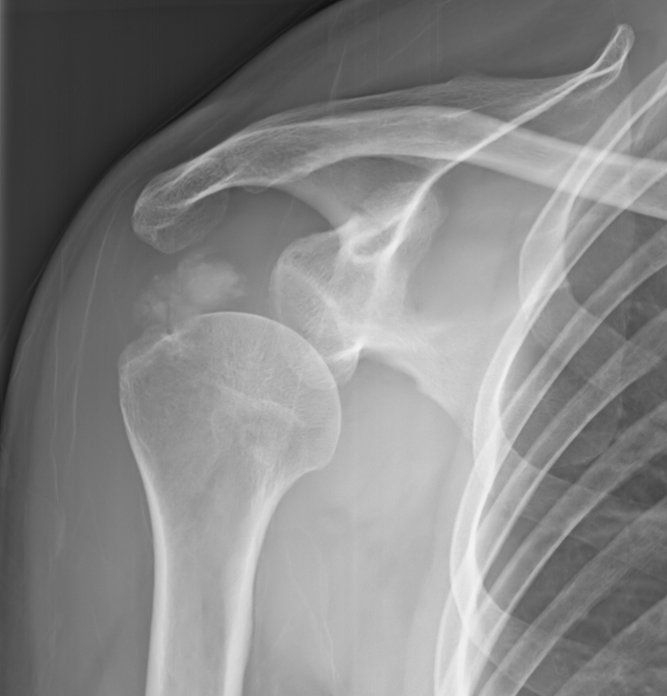

【109-1 醫學(六) 第73題】

59歲女性病人意外跌倒後,主訴左肩疼痛,X光檢查如圖,最可能之診斷為何?